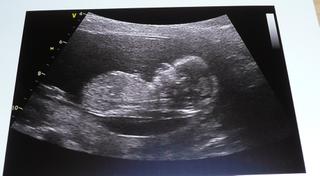

na gyndě vše o.k. 😵 😵 Byla jsme dneska u jiného doktora,na pokec byl skvělý,ale na Utz 🤐 Moje doktorka mi vždycky ukazuje dlouho mimíska,a vše ukáže.Tady to bylo dneska jen chviličku záběr na ručičku,mával mi 😵 😵 a záběr na srdíčko a to bylo vše 😅 nejdřív jsem byla z toho taková zklamaná,ale pak jsem si zase řekla,hlavně že jsem bobka malýho viděla 😵 No o fotečku jsem si neřekla a pohlaví doktor říkal,že je ještě brzy 🤐 🤐 No takže až příště,až půjdu ke své doktorce.

Ale holky mám aspon dvě fotečky z NT 😵 😵

Krásné fotky- celá mamča 😀

jejda kopi..to jsou krásné fotky 🙂 ..krásný človíček 🙂 🙂